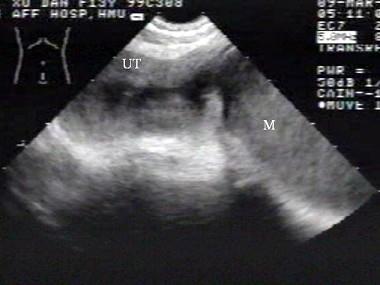

问题 女性,62岁,1周前疑诊为宫颈癌。超声检查如图,最可能的诊断是?(?)

选项 A.子宫肌瘤 B.宫腔积液并感染 C.子宫内膜癌 D.子宫内膜炎 E.正常声像图

答案 B